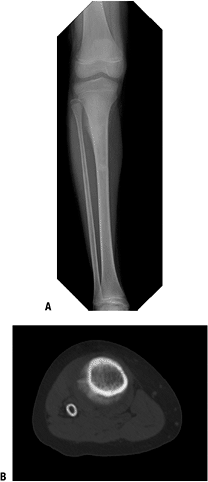

Figure 6.1-3 (A)

Plain anteroposterior radiograph of the pelvis shows a destructive

lesion of the left inferior pubic ramus. Note the metallic seeds

previously placed for treatment of prostate cancer in combination with

external-beam radiation 8 years prior. (B)

Axial CT image shows bony destruction and soft tissue mass extending

from pubic ramus. With the patient’s history, biopsy confirmed the

diagnosis of postradiation osteosarcoma. -